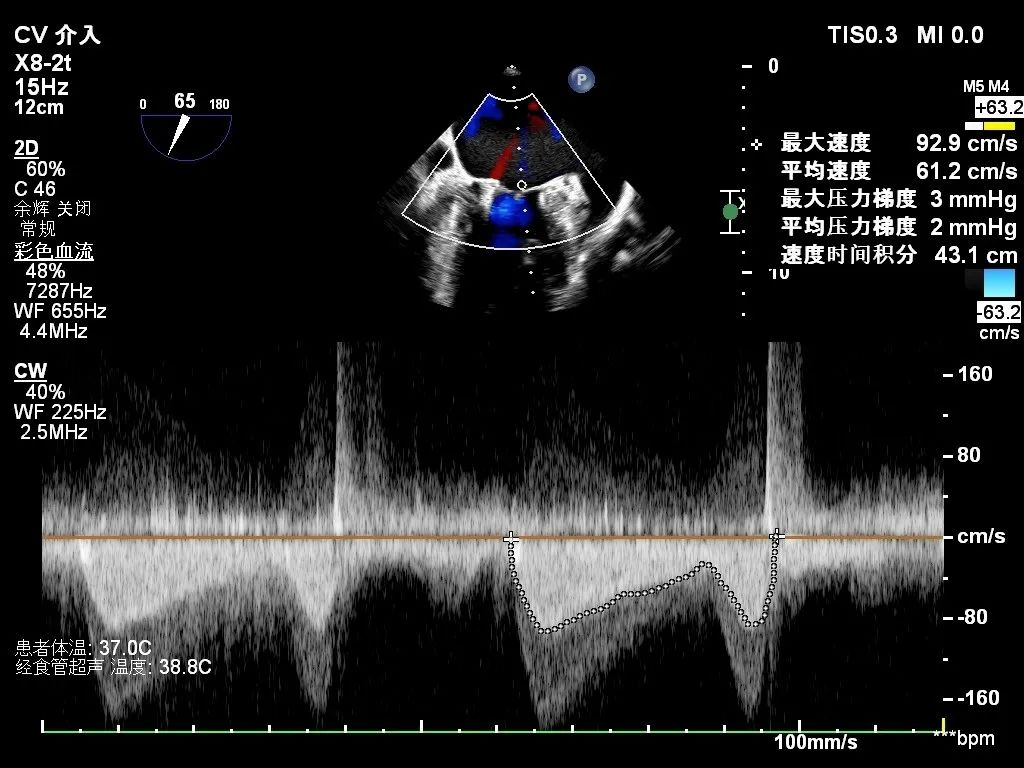

【术毕即刻超声】

针对该患者3区瓣下腱索较多,且有断裂腱索收缩期甩向左房侧,容易发生腱索缠绕等手术难点,彭杰成主任团队与徐健主任团队在麻醉和超声团队紧密配合下,先于3区靠内交界置入一枚短宽(SW0609)夹,解决内交界脱垂,然后并排于3区植入第二枚长宽(XW0612)夹解决残余脱垂病变。为平衡瓣叶张力,选择打开瓣膜夹20°进行释放,释放后无残余脱垂,二尖瓣反流降至微量,肺静脉逆流消失,效果显著。整个手术过程历时2小时左右,术后第二日解除股静脉绷带,患者下床活动自如,心功能明显改善。